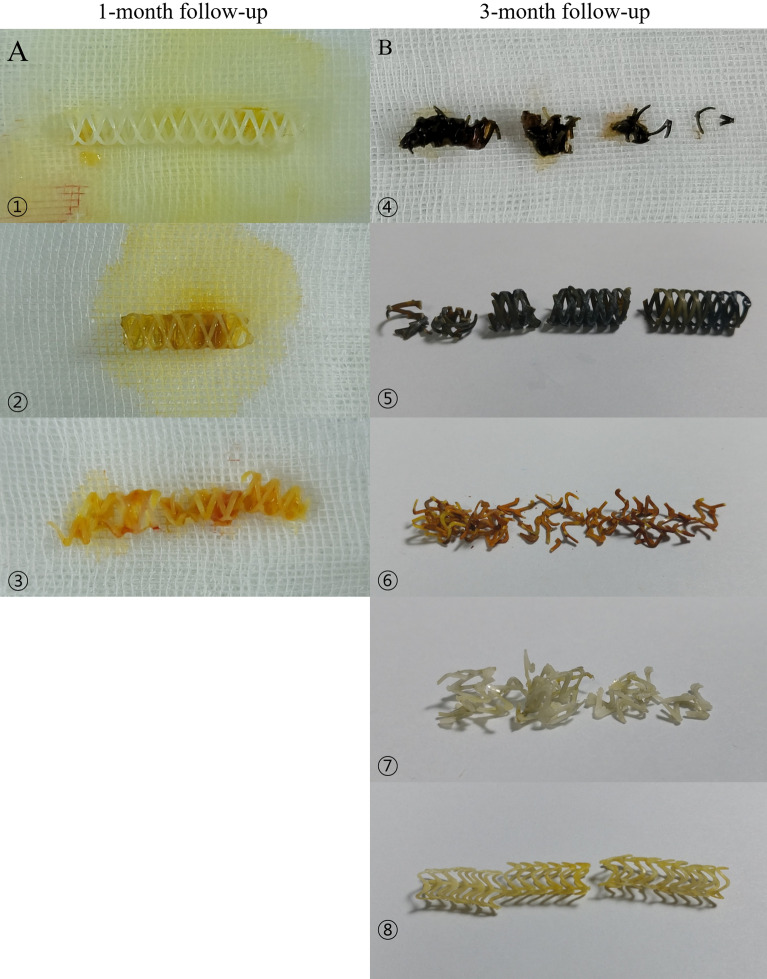

Macroscopic evaluation of 3D-printed biodegradable biliary stent

Macroscopic findings showed no definite change in color or integration of biodegradable biliary stents in the stent group at the 1-month follow-up (Fig. 7A). However, discoloration and fragmentation of biodegradable biliary stents were noted in the stent group at the 3-month follow-up (Fig. 7B).